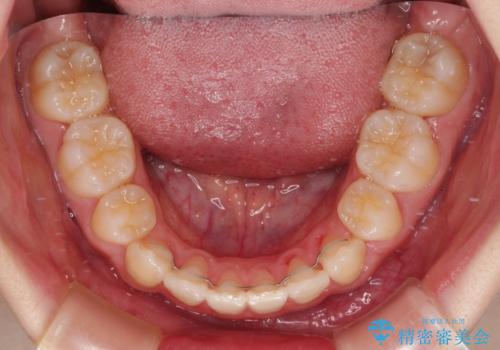

- 口元の閉じにくさを気にして来院された患者様です。

上下ともに歯列が前方に突出していたため、上下左右の第一小臼歯4本を抜去し、ワイヤー装置による矯正治療を行うこととしました。

舌の突出癖による影響もあったため、舌のトレーニングを並行して実施しました。